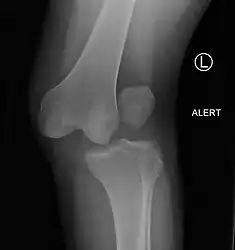

A Segond fracture seen on X-ray

Plain X-rays, CT scan, ultrasonography, or MRI may help with the diagnosis.[2][9] Findings on X-ray that may be useful among those who have already reduced include a variable joint space, subluxation of the joint, or a Segond fracture.[5]